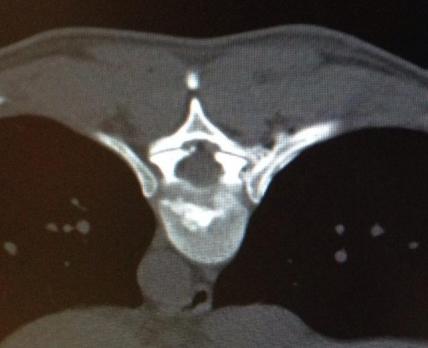

2 thin needles are guided to the joint space

The surgeon will insert a very small needle into the painful joint and will be guided by an X-Ray control. With the help of the needle where a small laser fiber can be inserted the surgeon can now desolate the nerve which causes the pain.